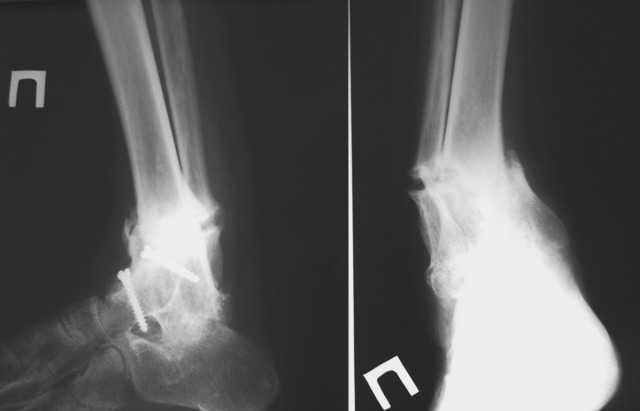

Уважаемые коллеги! Обращаюсь за советом. Пациентка, страдающая ревматоидным артритом, 2 года назад была оперирована по поводу вторичного деформирующего артроза голеностопного сустава с варусной деформацией на этом уровне.

В то время деформация была обусловлена деструкцией тарана, поэтому был выполнен артродез по Кэмпбеллу. Спустя 2 месяца после операции сформировался костный анкилоз голеностопа в физиологическом положении+анкилоз задней фасетки подтарана, пациентка была в восторге, т.к. до этого намаялась со стоптанной обувью, нарушенной походкой, с ортезами и, соответсвенно, с потертостями и гиперкератозами. Тем не менее, нынче обращается с ТЕМИ ЖЕ ПРОБЛЕМАМИ, которые исподволь нарастали в течение 1,5-2 месяцев. Делаем снимки и, о ужас, видим лоозеровскую зону выше анкилоза, клинически тот-же варус. Ясно, что лоозера срастим как-нибудь, но, наверное, надо-бы еще что-то сделать, дабы избежать повторов. PS. С пациенткой доверительные, хорошие отношения.